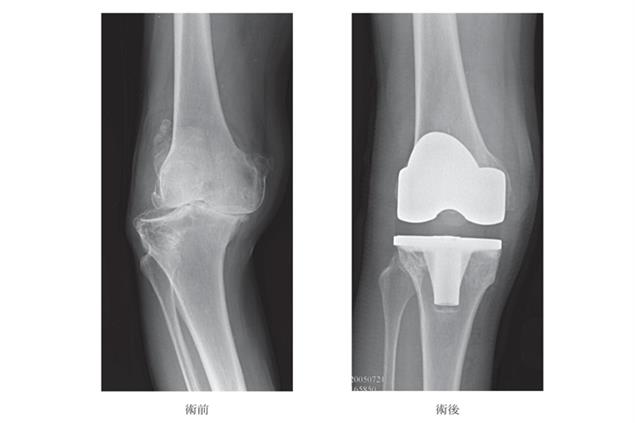

自己的膝蓋自己救》置換人工膝關節是治療「退化」性膝關節炎的最佳方式?

當膝關節病變進展到末期時,關節面軟骨嚴重磨損,甚至出現變形,導致疼痛、行動不便、功能受限,會嚴重影響生活品質。...